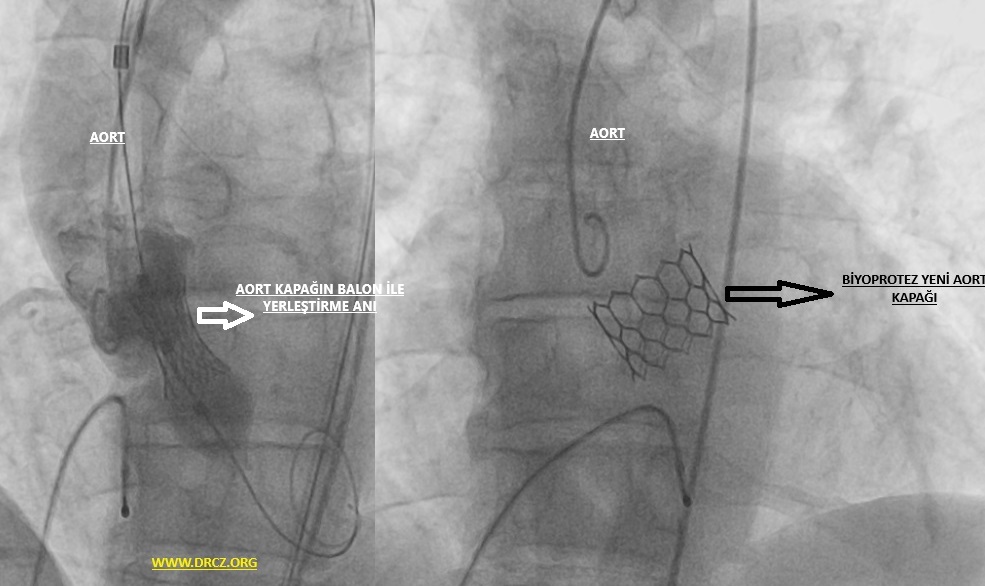

TAVI Uygulaması Nedir?

(TAVI), aortik kapak stenoz (darlık) tedavisi için kullanılan minimal invazif bir tıbbi işlemdir. TAVI işlemi sırasında, genellikle kasık bölgesinden veya göğüs duvarından bir kateter, hastanın arteriyel sistemine yerleştirilir ve aort kapağına ulaşılır. Sonra bu kateter aracılığıyla eski ve hastalıklı aortik kapak yerine yeni bir protez kapak yerleştirilir. Yeni kapak açılarak kanın daha etkili bir şekilde pompalanmasına yardımcı olur. TAVI, özellikle yüksek risk taşıyan veya açık kalp cerrahisi için uygun olmayan hastalar için önemli bir alternatif sunar ve genellikle daha hızlı bir iyileşme süresiyle ilişkilendirilir.